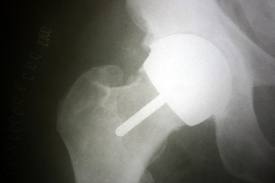

Outcomes of hip resurfacing in a professional dancer: A case report

A new surgical option (hip resurfacing arthroplasty) is now available for younger patients with hip osteoarthritis. A more aggressive rehabilitation program than the typical total hip arthroplasty protocol is needed for active individuals.

This case report describes interventions used to maximize function in a 46-year-old professional dancer after hip resurfacing with a progressive therapeutic exercise program. Exercise choices were selected to address dance-specific requirements while respecting healing of the posterior capsular incision.